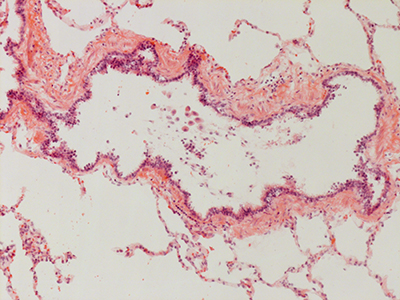

31 Year Old Adult Human Lung D003 H&E